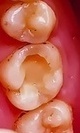

「右下の奥歯が冷たいものでしみる」とご相談いただいた患者様。拝見したところ、古い詰め物(コンポジットレジン)の下ではなく、隣の歯と接する面に小さな虫歯ができていました。

このタイプの虫歯は、進行すると歯の内部に感染が広がり、最終的には神経にまで達するリスクがあります。さらに、隣接面という場所柄、隣の健康な歯まで虫歯にしてしまう可能性もあるため、早急な治療が必要だと診断しました。

拝見したところ、左上の奥歯(第2小臼歯/5番)には、隣の歯と接触する部分に虫歯ができていました。

このまま虫歯を放置すると歯の内部が虫歯菌に感染し、痛みが生じたり神経が死んでしまったりする可能性があります。さらに隣の歯も虫歯になるおそれがあるため、早急に虫歯部分を除去する必要があると診断しました。

まずは麻酔を行ってから、虫歯を取り残さず健康な歯質を削る量も最小限になるよう、虫歯を染め出せる染色液を使って丁寧に処置を進めています。

取り残しがないことを確認しつつ歯の形を整え、ゴム製の歯型をとる材料「シリコーン印象材」で型どりを行いました。シリコーン印象材は従来の印象材に比べて精細に型どりができるため、詰め物の適合性を高める目的で使用しています。

周りの歯になじんだ自然な仕上がりで、噛み合わせも問題ありません。